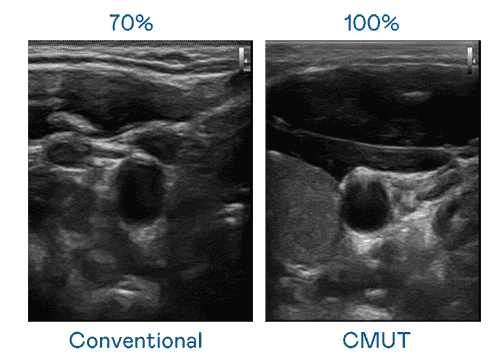

CMUT 技术是一种用电容式微机电元件来产生超音波讯号的技术。。。。与传统 PZT 压电式技术相比,,,CMUT 频宽增加 30%,,,更宽频的超音波讯号让影像解析度大幅提升,,,,是实现高影像品质医疗超音波扫描、、、、促进精准医疗发展的关键技术。。。。

大频宽带来超清晰影像

超音波影像的解析度高低,,,首先取决于探头能发出的讯号频宽。。z6尊龙 CMUT 可提供高清晰的超音波讯号,,提供高频宽、、、、高灵敏度、、、、影像纹理细节更高的超音波影像,,协助医护人员缩短影像判读时间及利用精准的医疗影像进行诊断。。。